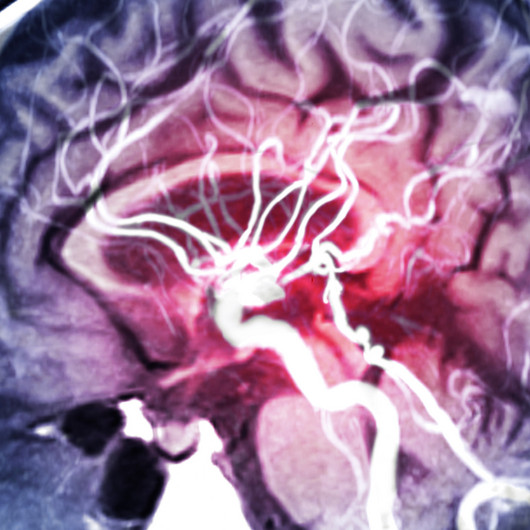

Die Folgen eines Schlaganfalls sind von Patient zu Patient sehr unterschiedlich. Eines ist jedoch bei sämtlichen Verläufen gleich: Die Betroffenen benötigen eine umfassende und sofortige Therapie. Deshalb beginnen auf unserer Stroke Unit innerhalb von 24 Stunden nach der Aufnahme krankengymnastische, logopädische, ergotherapeutische und wenn notwendig neuropsychologische Behandlungen.

Nach der Akuttherapie auf der Stroke Unit können Patienten mit schwersten Hirnschädigungen in unserer neurologischen Frührehabilitation weiter behandelt werden. Dabei arbeitet ein interdisziplinäres Team Hand in Hand: Es besteht aus Physiotherapeuten, Ergotherapeuten, Neuropsychologen, Logopäden sowie therapeutische Pflegekräfte mit speziellen Zusatzqualifikationen. In enger Kooperation mit den Sozialarbeitern des Hauses organisieren wir auch eine direkte Verlegung in geeignete Rehabilitationskliniken.

Unsere neurologische Frührehabilitation verbessert die Chancen, Spätfolgen eines Schlaganfalls zu minimieren oder sogar zu vermeiden. Wichtigstes Ziel ist, die Betroffenen schnellstmöglich ins aktive Leben zu begleiten. Die schrittweise Wiedererlangung ihrer Selbstständigkeit steht dabei im Mittelpunkt. Dies erfordert Zeit, Geduld und Training. Für Angehörige ist wichtig zu wissen, dass sie bei zahlreichen Therapien herzlich willkommen sind. Denn auch sie erlernen hierbei den richtigen Umgang mit den Folgen des Schlaganfalls und verinnerlichen wichtige Verhaltensweisen, die das Risiko eines erneuten Schlaganfalls mindern können.